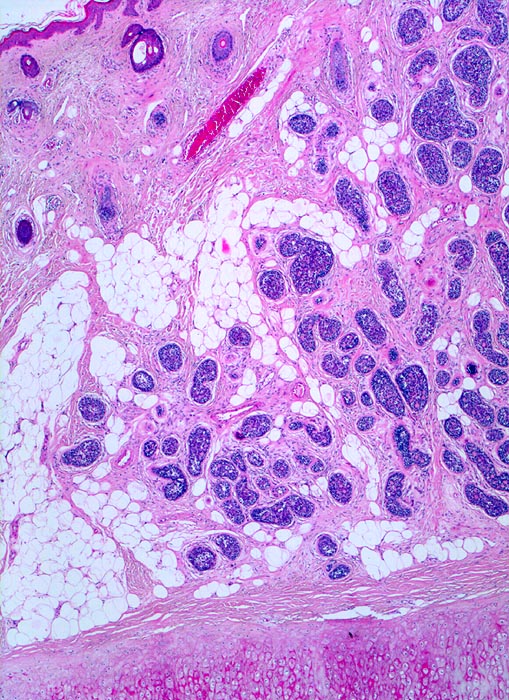

PathoPic ID 3962 - adenoidzystisches Karzinom der Haut

adenoidzystisches Karzinom der Haut

maligner Tumor

Haut, Kopf

Haut

Solide scharf begrenzte unregelmässig in der Dermis und im subkutanen Fettgewebe verteilte Tumorzellnester. Unten im Bild Anschnitt des Ohrknorpels.

Tumor an der Ohrmuschel

Histologie

25